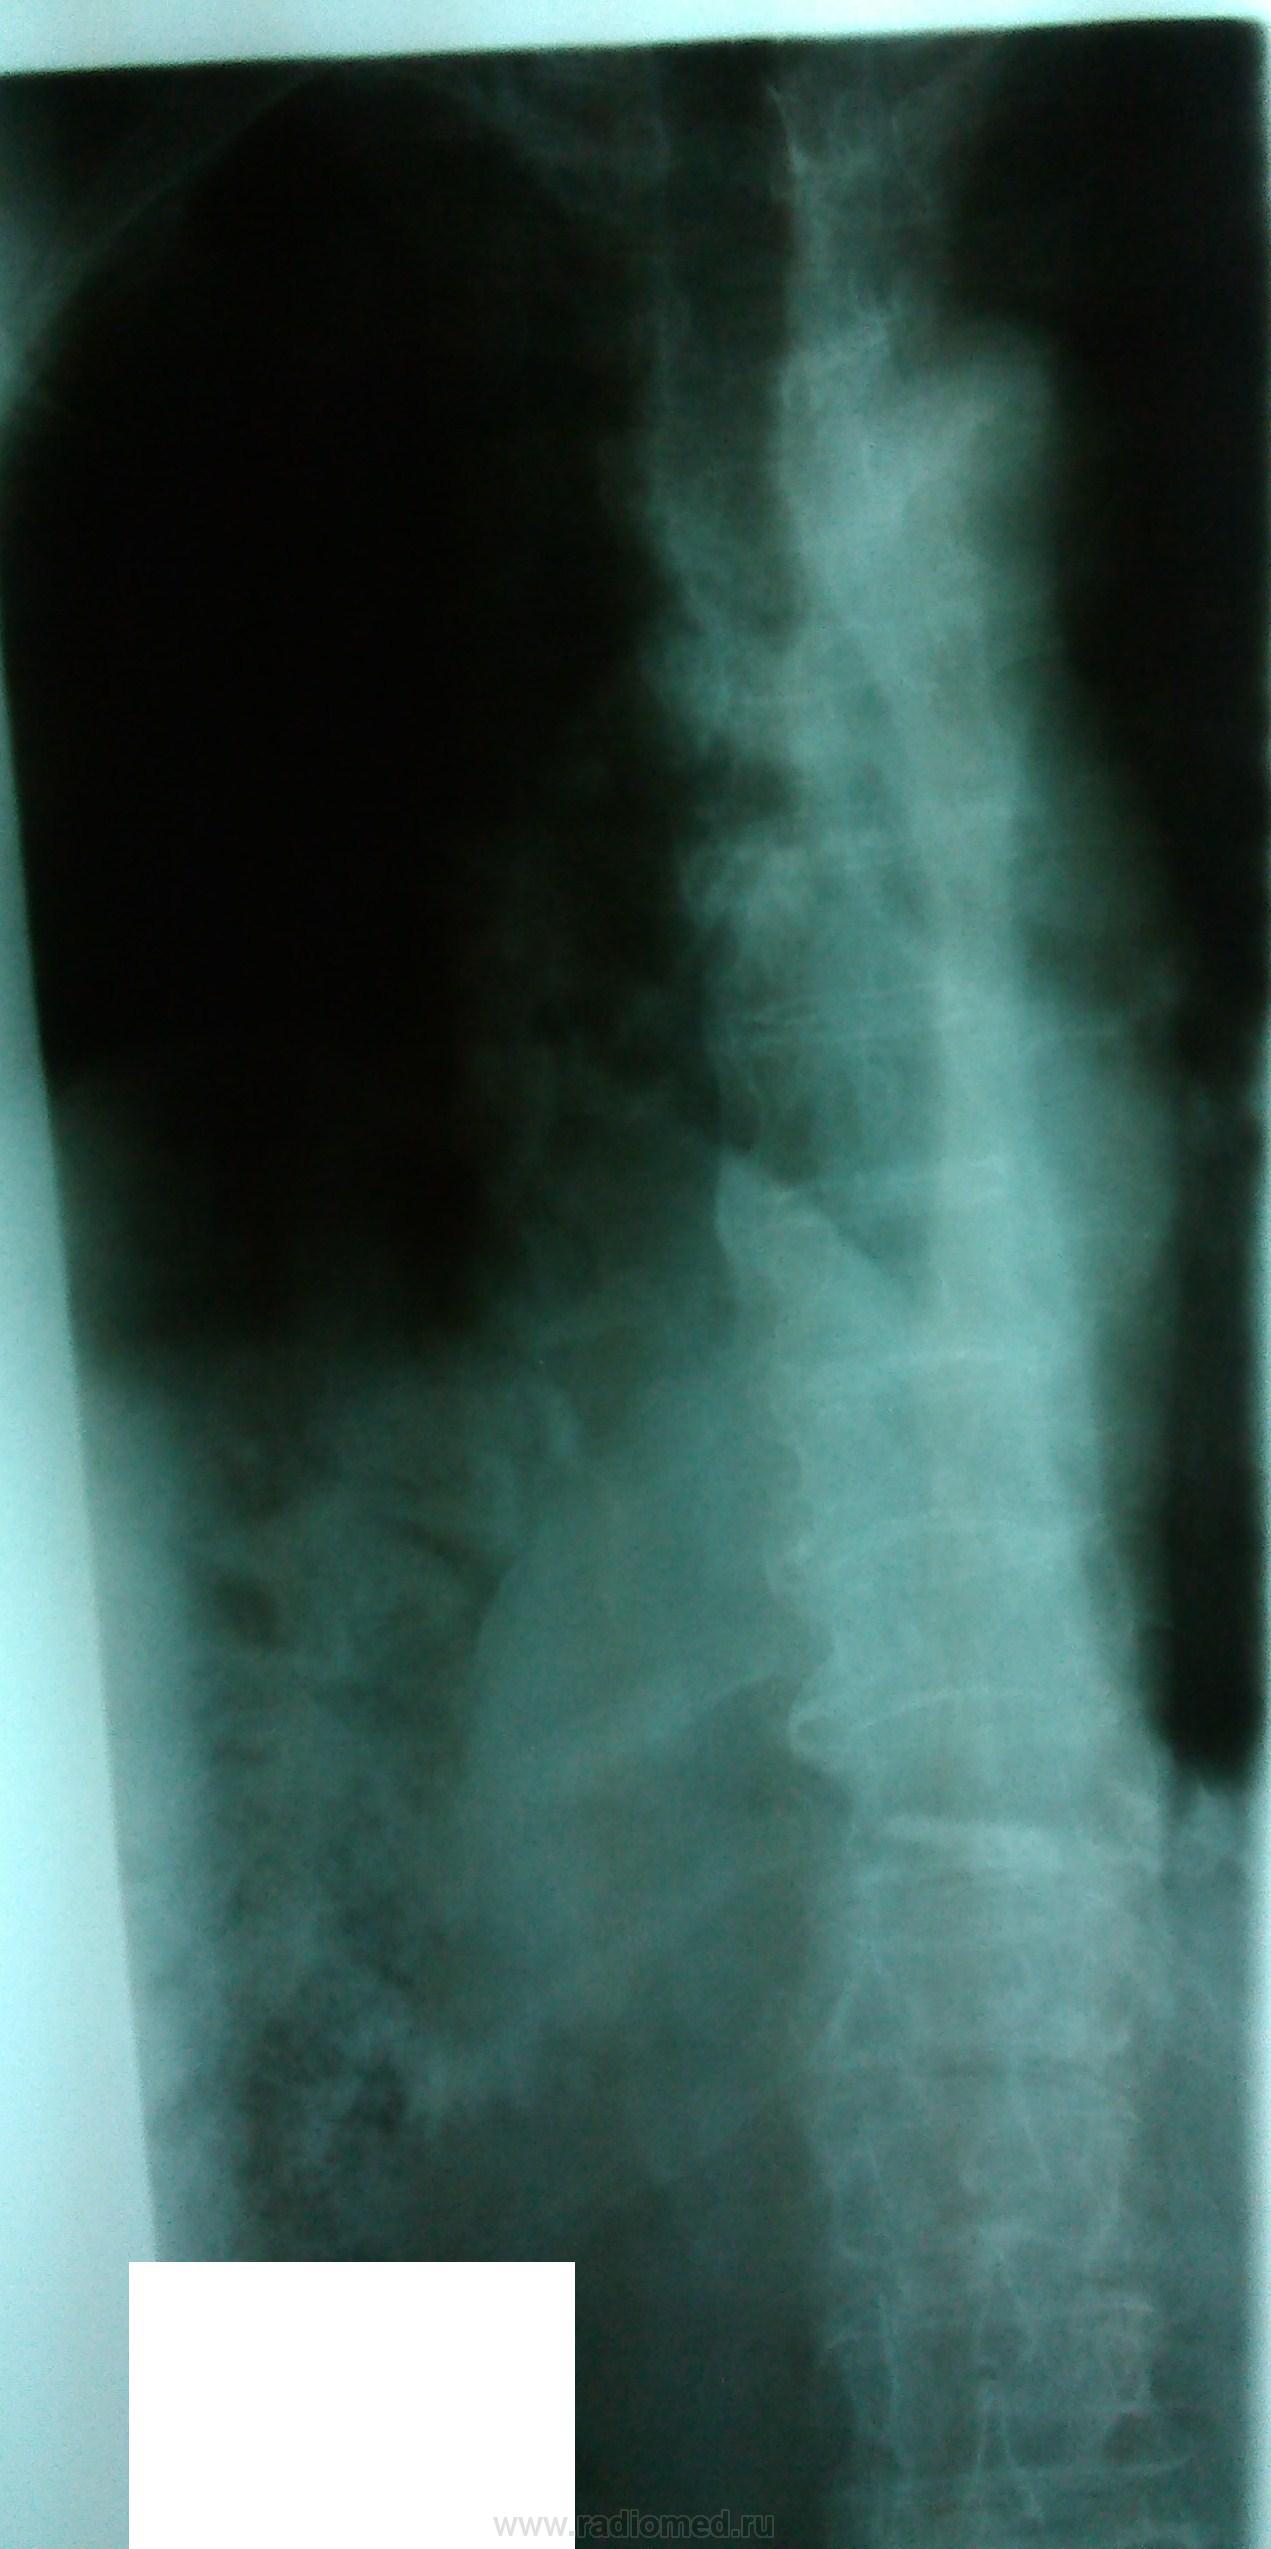

Пациентка, 83 года. DS: ИБС: Атеросклеротический кардиосклероз. Выраженный кифоз грудного отдела позвоночника. Какие мнения по поводу заключения?

Смотрится как релаксация правого купола диафрагмы

Центральный рак нижнедолевого бронха правого легкого, ателектаз нижней доли правого легкого, мтс в кости аксиального скелета грудной клетки.

Как-то слишком округло для ателектаза на боковом снимке, и дуга аорты на месте..

+1. По боковой проекции,  в базальном отделе  кпереди от позвоночника, тень округлой формы- MTS ? Необходимо дообследование, в каком виде выполнить его зависит от возможностей: оптимально КТ грудной клетки. При отсутствии линейная томография на правый корень и структуру округлой тени справа. Находки надо связать с клинико-лабораторными данными.

Господа коллеги, какая релаксация, какая связь с клинико-лабораторными данными?

Посмотрите на ребра...

Прямой снимок недоекспонированый. Позвоночника совсем не видно. Да и боковой недостаточно жесткий. Предлагаю начать с переделки снимков. А в целом, подозрения на онко поддерживаю.